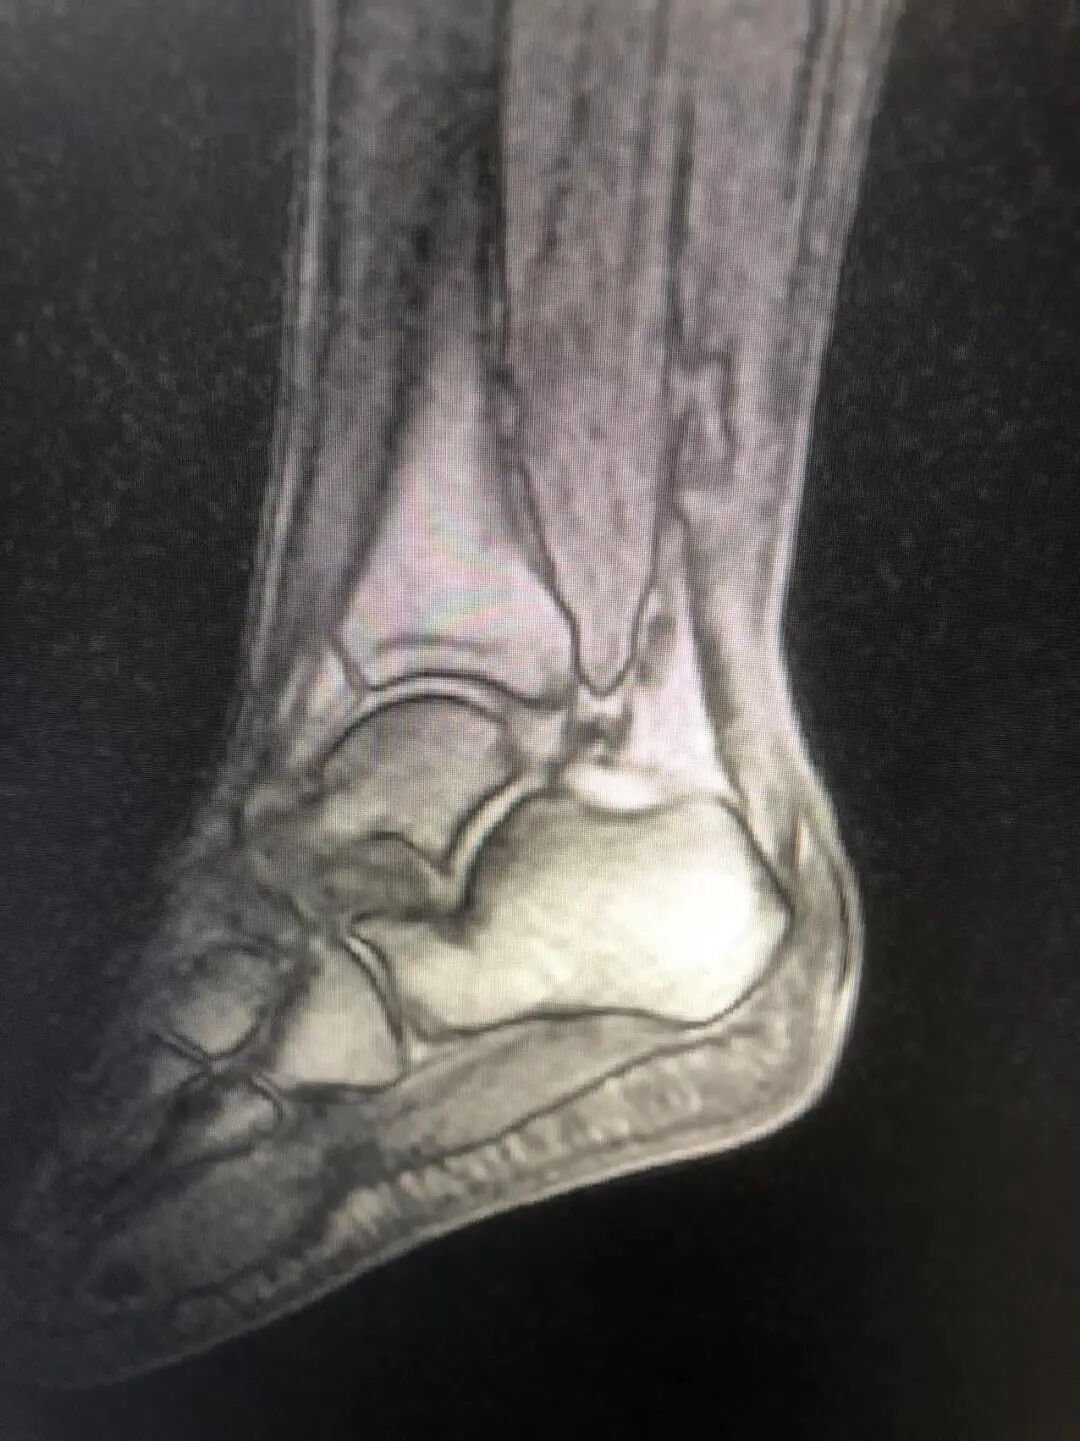

案例2:患者男性,41岁,因“弹跳后出现左足跟肿痛、左踝活动受限6小时”入院,查体:左下肢跛行,左足跟后侧局部肿胀,跟腱处凹陷,压痛,左跟腱区空虚,左踝关节主动背伸活动不能,被动活动好,Thompson征阳性